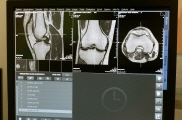

그리고 영상을 통해 염증수치 검사를 하는 방법들도 있습니다. 영상 검사에는 X-레이, CT 스캔 및 MRI 스캔과 같은 영상 검사를 사용하여 관절이나 장기와 같은 신체의 특정 부분에서 염증을 식별할 수 있습니다. 또한 고주파 음파를 사용하여 내부 장기 및 조직의 이미지를 생성하여 확인하고 관절, 힘줄 및 기타 연조직의 염증을 식별하는 데 사용할 수 있는 초음파 검사가 있습니다.